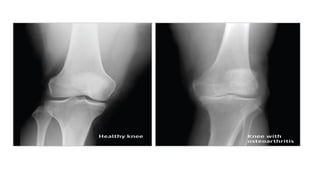

 Degeneration of the articular cartilage is the principal pathologic

Osteoarthritis

• Early radiographic changes in osteoarthritis include

small osteophytes at joint margins, focal narrowing of

joint spaces, subchondral bony sclerosis in the

segment affected by joint-space loss, and an absence

of periarticular demineralization.

• Later changes include large and more extensive

osteophytes, more pronounced focal joint-space

narrowing, subchondral bone cysts with sclerotic

margins, and the formation of bony ossicles (in soft

tissues adjacent to the joint or within the joint cavity.

• Advanced changes include extensive joint-space loss

and joint deformity.